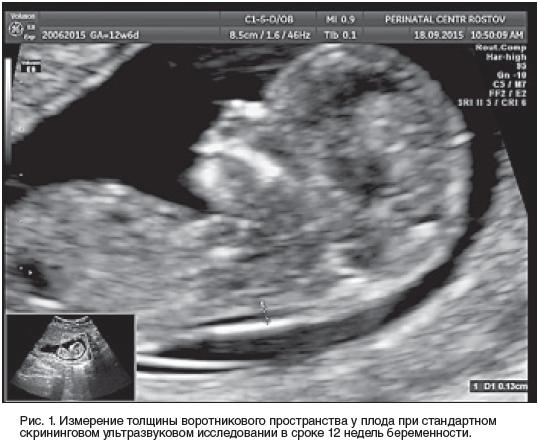

Норма воротниковой зоны в 12

Норма воротниковой зоны в 12 119 фото